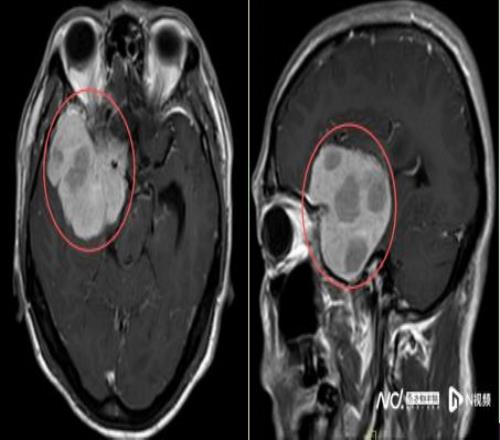

2025年10月起,他在跑步途中頻繁在轉(zhuǎn)彎處摔倒,偶爾還感覺一側(cè)手腳乏力,起初并未放在心上。但隨著摔跤次數(shù)不斷增多,又無明顯誘因地出現(xiàn)持續(xù)一周的頭痛,他和家人終于警覺起來。同年11月中旬,陳叔家人帶他在當(dāng)?shù)蒯t(yī)院做了一次檢查。MR結(jié)果如晴天霹靂:右額顳部蝶骨嵴占位病變,大小約5.5x6.6x5.8cm,考慮腦膜瘤。

鑒于腫瘤體積巨大、位置較深,考慮為右側(cè)額顳蝶骨嵴內(nèi)側(cè)型巨大腦膜瘤,腫瘤突入垂體窩和斜坡,環(huán)繞頸內(nèi)動脈及分支、視神經(jīng)等重要結(jié)構(gòu),壓迫腦干。手術(shù)難度是神經(jīng)外科最復(fù)雜的手術(shù)之一,猶如刀尖上行走,且已出現(xiàn)進(jìn)行性神經(jīng)功能缺損癥狀:肢體乏力,視力受損,視物重影等,病情復(fù)雜、手術(shù)風(fēng)險極高。